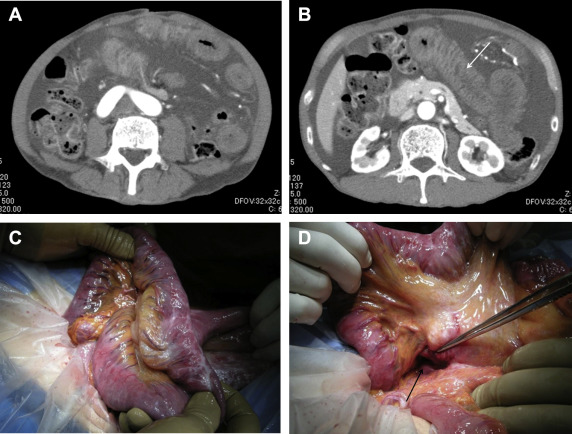

Table 5 shows a comparison of the clinical features of IH between patients who underwent antecolic versus retrocolic RY. These variables (patient age, sex, cancer stage, degree of lymph-node dissection, operative time, intraoperative bleeding, and BMI at LG) did not significantly differ between the two groups. The median interval between LG and IH was 36.1 months (range 15.5–92.2 mo) in the antecolic group, and 8.4 months (range 0.2–28.9 mo) in the retrocolic group (p < 0.01). The most common symptom in our study was abdominal pain, which was observed in 14 of the 15 patients; three patients suffered repeated abdominal pain until the diagnosis of IH. The remaining patient experienced repeated, massive ascites three times without any other symptoms ( Figure 1). Because this ascites disappeared without treatment within a few days, the IH responsible for the ascites was missed by an outside hospital during the first two events despite other imaging findings, such as whirl sign, biliopancreatic limb dilatation, and localization of the bowels to the left upper quadrant on computed tomography (Figure 2). Also, 3 of the 15 patients (all of whom had undergone antecolic RY) had histories of acute pancreatitis due to biliopancreatic limb obstruction.

Abdominal enhanced computed tomography showed (A) significant ascites and (B, ...

Figure 1.

Abdominal enhanced computed tomography showed (A) significant ascites and (B, arrow) an edematous Roux limb. Both findings had been seen previously (2 mo before and again 2 wk before the episode shown), but had temporarily vanished without any treatment. (C) Operative findings revealed an edematous Roux limb, which was not ischemic. Ascites had been induced by the obstruction of mesenteric venous return. (D) The small bowel had passed through Petersens defect (arrow) from the right side to the left side.